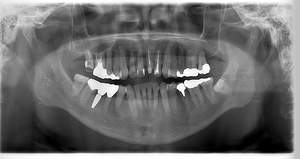

レントゲン写真

- Befor

- After

| 年齢 | 50代・男性 |

|---|---|

| 主訴 | 左上7番 左下5番7番 |

| 治療内容 | ・インプラント埋入 ※1:GBR(骨造成)・・・骨再生誘導法。骨の高さや厚みを人工骨や人工膜などを使用し再生する方法 |

| 治療費 | 合計:1,809,500円(税込) ■内訳 ・左上7番 ・左下5番7番 |

| 治療期間 | 左上7番約1年 左下5番7番約10ヵ月 |

| 治療方針 | 左上7番は昔他院で被せものをしており、被せものの中が歯ぐきの中まで虫歯になっていたため抜歯せざるを得ない状態だった。抜歯と同時に骨造成を行い、骨が出来るまで4ヵ月待ってからインプラントを埋入した。 ※2ポンティック・・・歯のない部分を補うダミーの歯。 |

| 担当者所見 | 元々金属の被せものが多く入っていたため、2次カリエス※3が多かった。今回は金属ではなく、ジルコニアを使用し、2次カリエスにならないよう、患者様にはブラッシング指導とメンテナンスの重要性をお伝えした。 ※3二次カリエス・・・詰め物や被せものを入れた歯が虫歯になること。 |